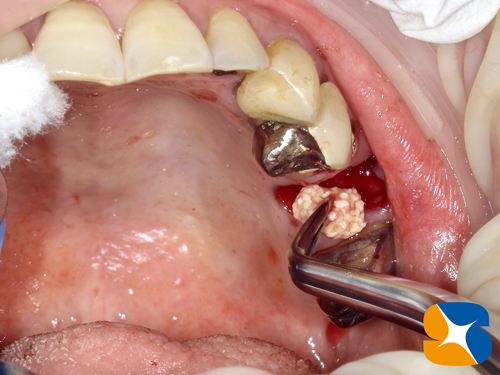

抜歯を行なったところ、2本の歯根が見事にバラバラに折れた状態で歯茎の中に突き刺さっていました。口腔ガン?と心配されていましたが問題はありませんでした。これから折れた歯根を摘出していきます。

抜いた銀歯も恐ろしい状態になっていました。